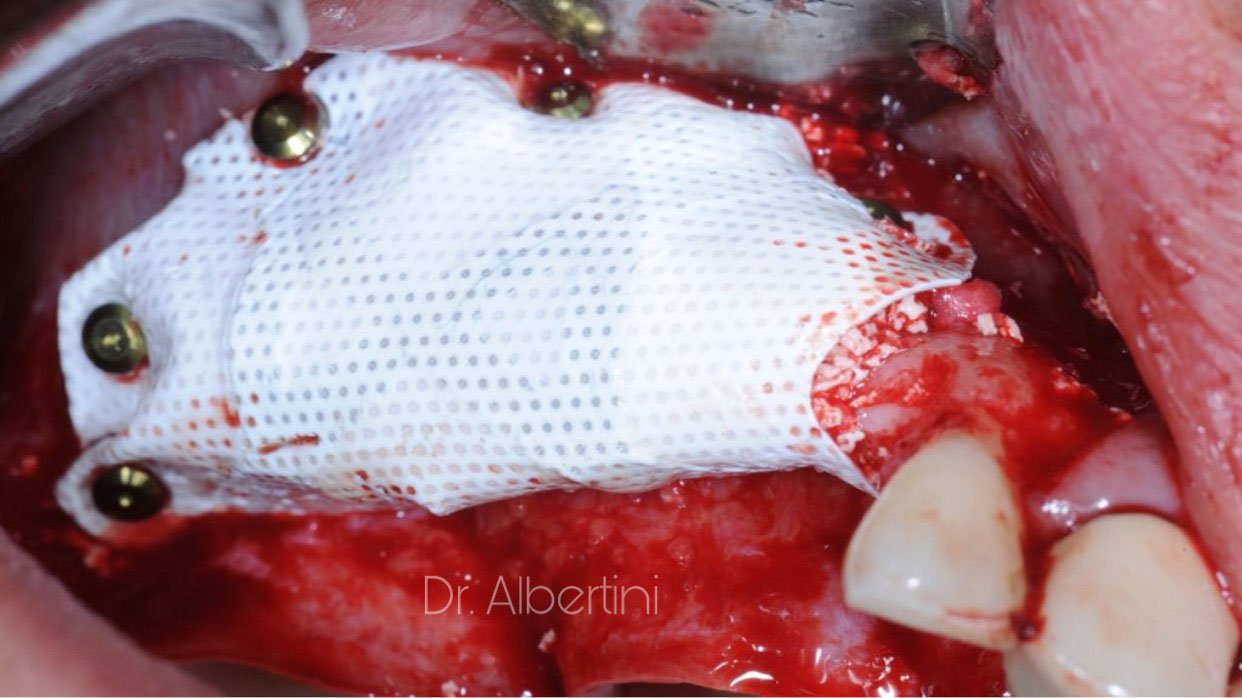

Dr. Mateo

Albertini